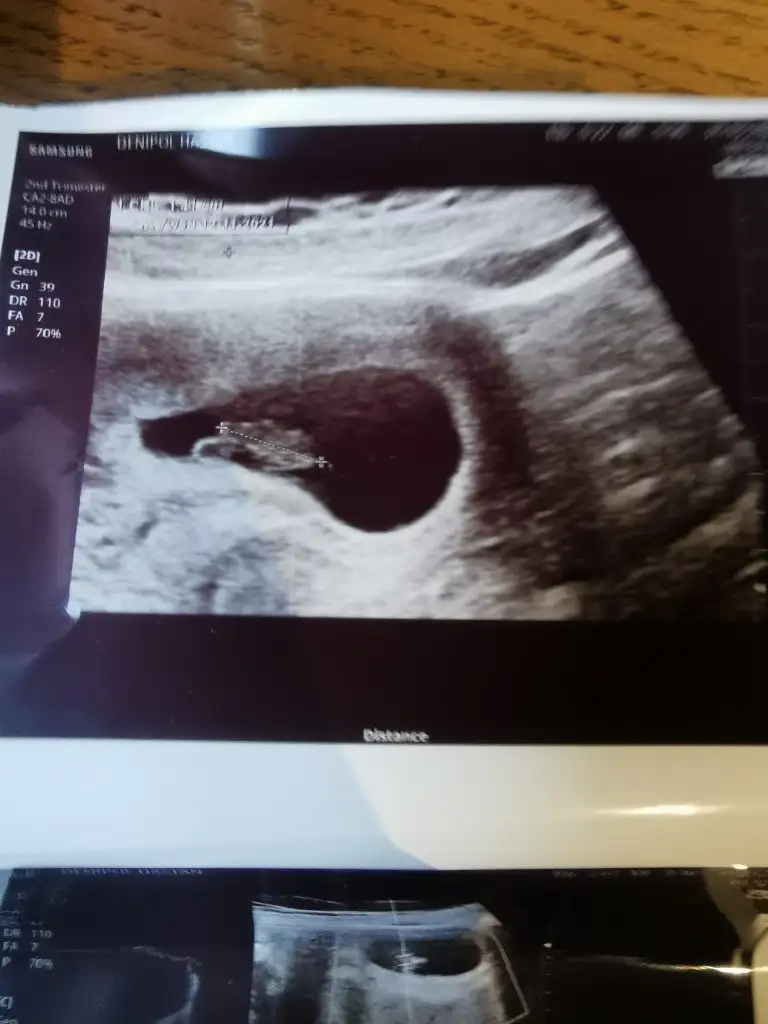

ErkekMerhabalar 7 hafta 5 günlük burada cinsiyet tahmini alabilir miyim bende karından ultrason abdominal. Eki Görüntüle 2814048 şimdiden teşekkür ederim